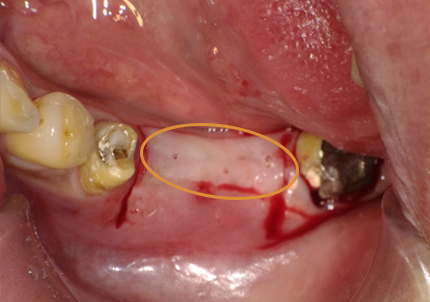

【ソケットシールドテクニックにて頬側骨の形態を維持する (右の様な骨のへこみを作らない)】

【通常の抜歯により唇側骨(外側の骨)が吸収してへこんだ症例】

※ 通常、ソケットシールドテクニックは前歯部領域に用いるが小臼歯部でも採用しました